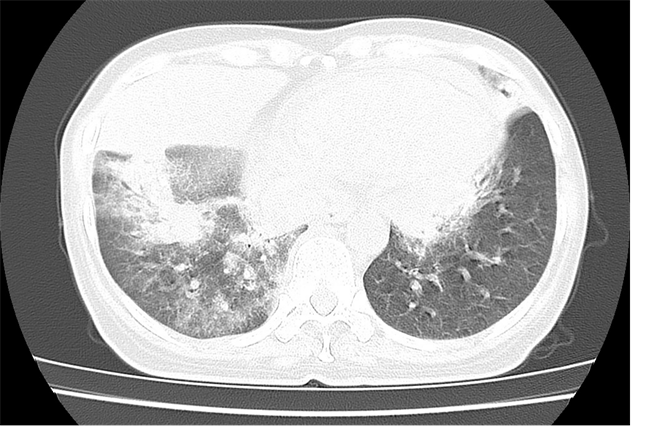

该患者患有“干燥综合征”,反复高热、寒战。入院2天前再次出现发热症状,并伴有胸闷、喘息,到我院急诊行肺CT检查见大范围肺部感染伴随实变,入院后病情急剧恶化,SPO2降至69%,BP64/42mmHg,体温高达40℃,患者持续高热,全身炎症反应重,血流动力学极不稳定——需要2种血管活性药较大剂量仍难以维持血压,迅速出现呼衰、肾衰、心衰等多器官功能面临衰竭表现,医疗团队判断是由脓毒症引发的“细胞因子风暴”在肆虐。

患者入院时胸部CT影像